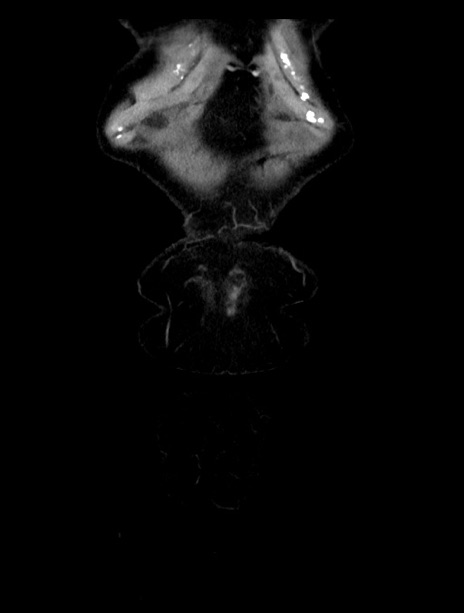

症例23(冠状断像)

【症例】70歳代女性

【主訴】下腹部痛・嘔吐

【現病歴】2日前より腹痛あり。昨日嘔吐あり。症状改善しないため来院。

【既往歴】胃GISTに対して胃部分切除後。

【身体所見】BT 37.1℃、BP 128/77mmHg、腹部:平坦・軟、下腹部に圧痛あり。

【データ】WBC 10200、CRP 0.31